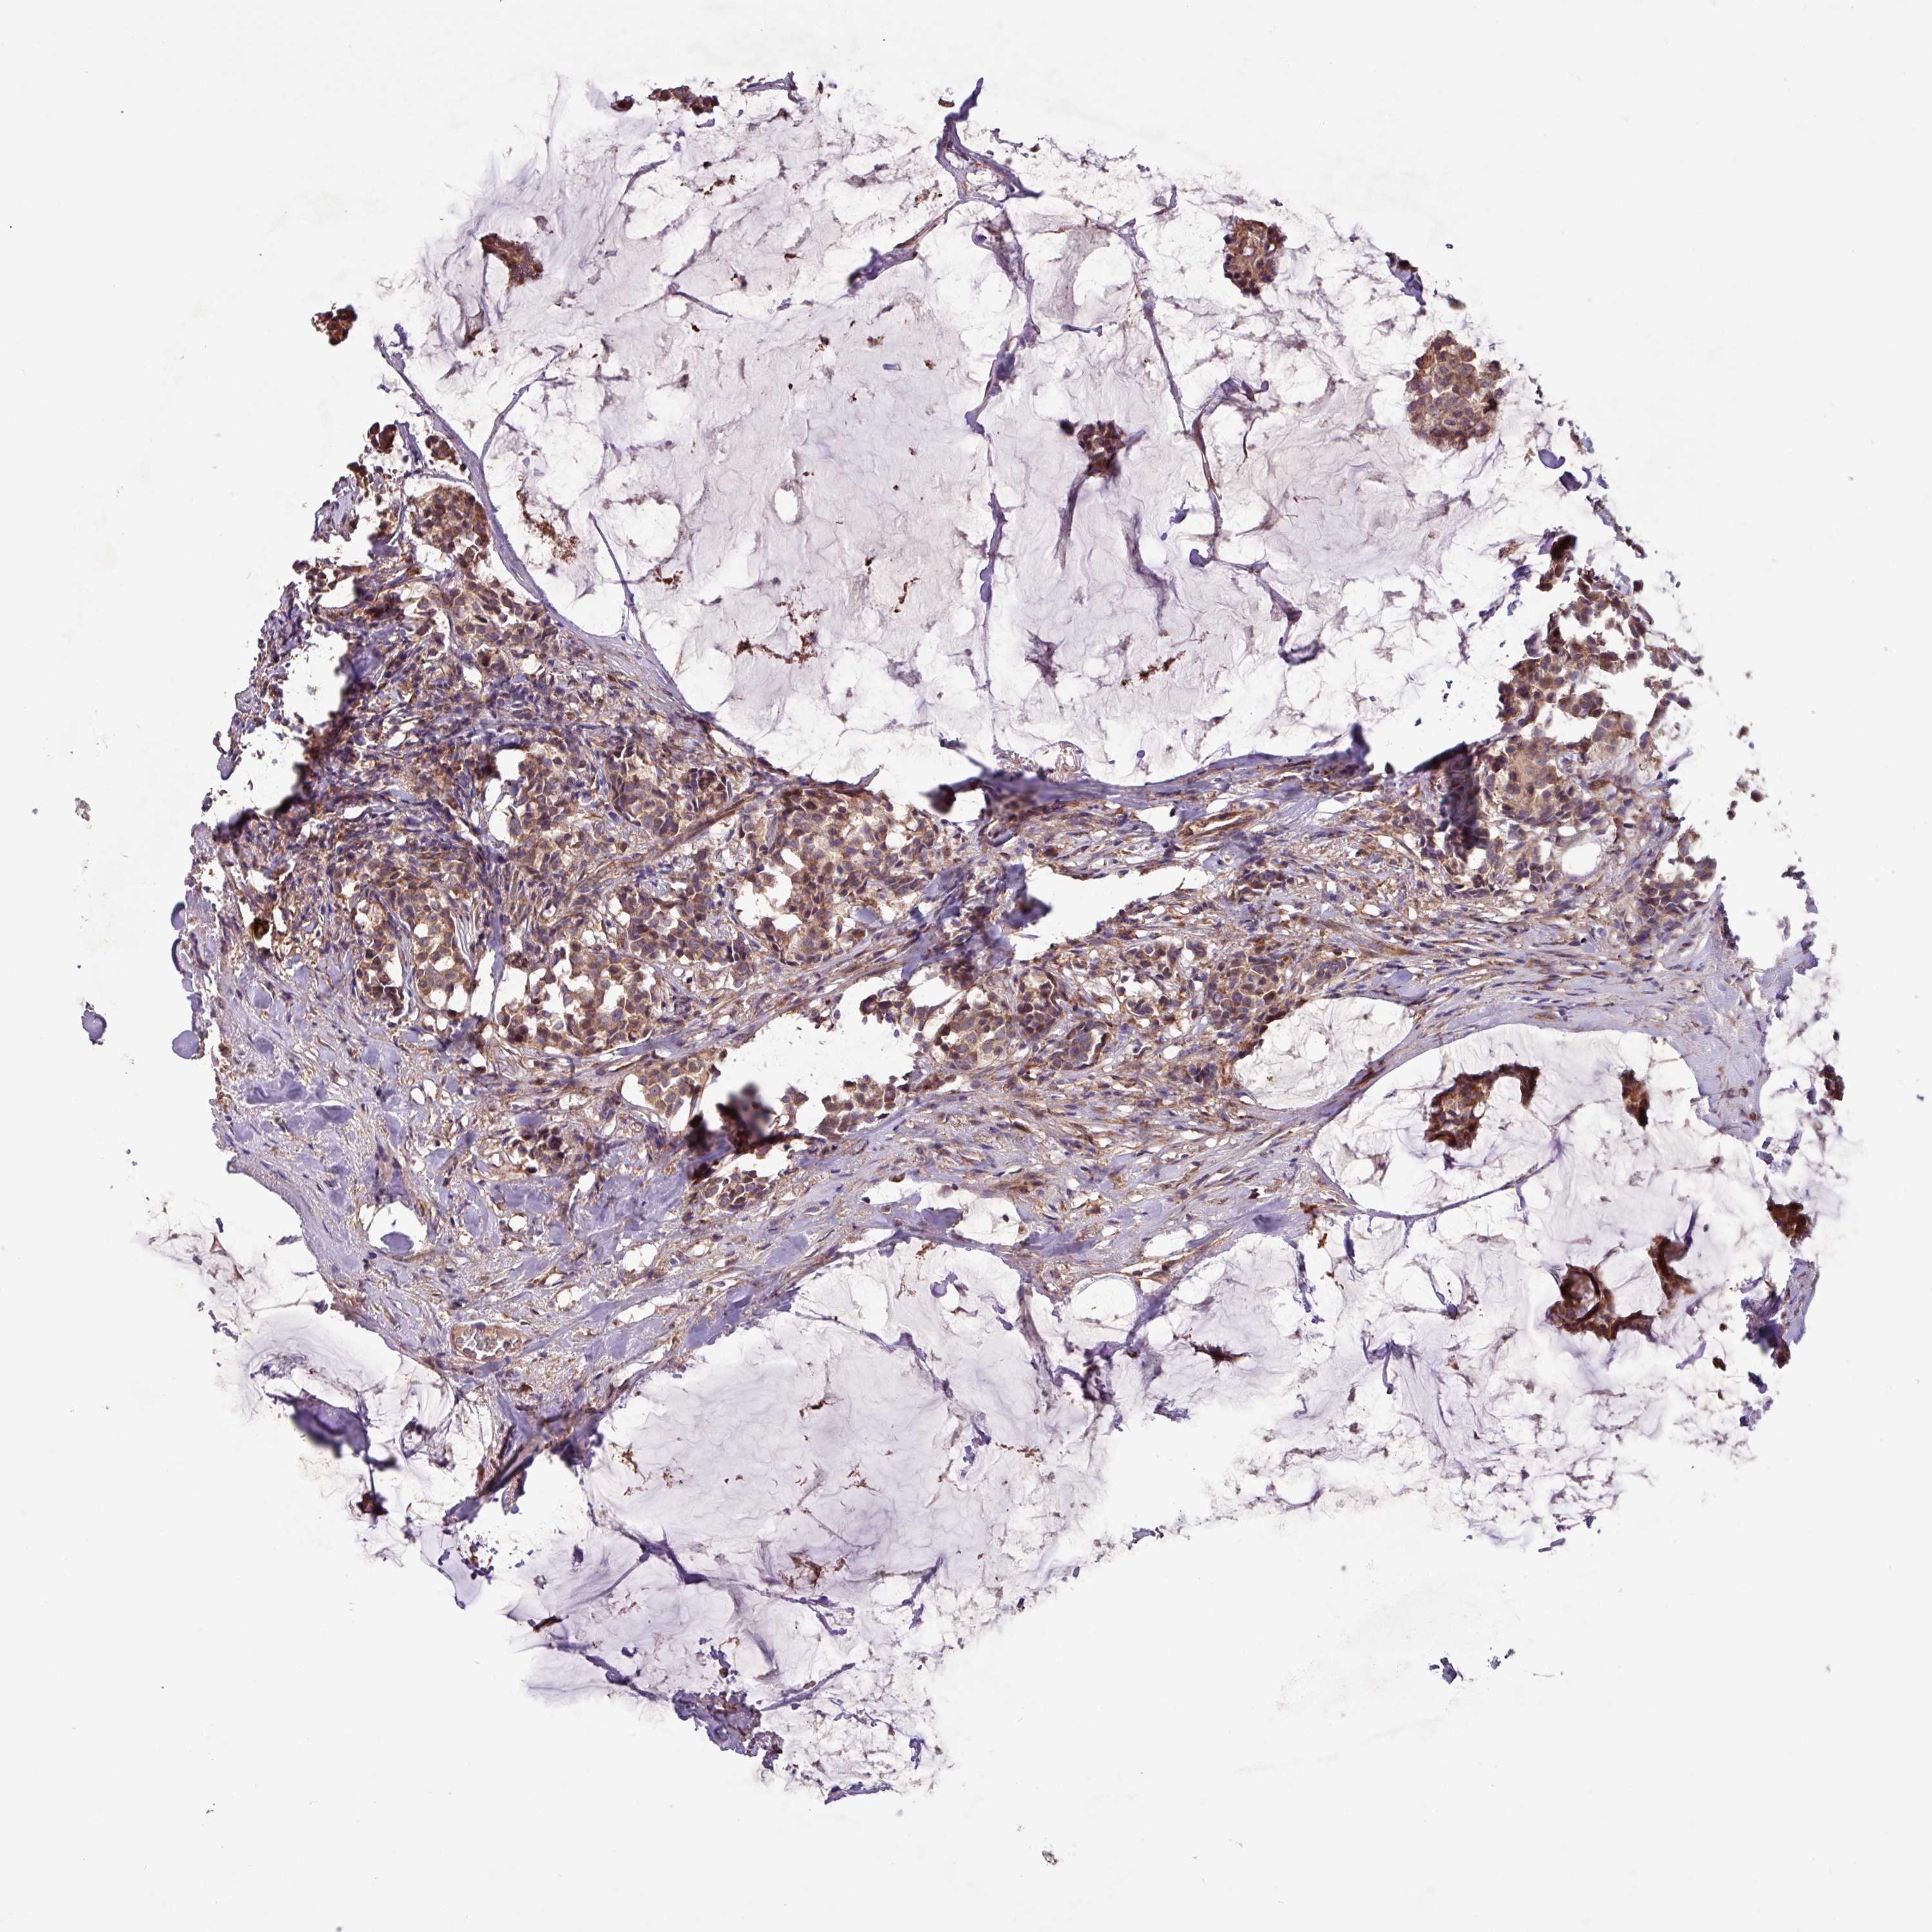

CANCER BREAST CANCER Show tissue menu

BRCA TCGA BRCA VALIDATION PROTEIN EXPRESSION

Breast cancer

Human cancer

PTPRQ is not prognostic in Breast Invasive Carcinoma (TCGA)

TCGA RNA samplesi

RNA-seq data is reported as average FPKM (number Fragments Per Kilobase of exon per Million reads), generated by the The Cancer Genome Atlas (TCGA) .

Normal distribution across the dataset is visualized with box plots, shown as median and 25th and 75th percentiles. Points are displayed as outliers if they are above or below 1.5 times the interquartile range. FPKM values of the individual samples are presented next to the box plot.

Average pTPM 0.4

Number of samples 1022